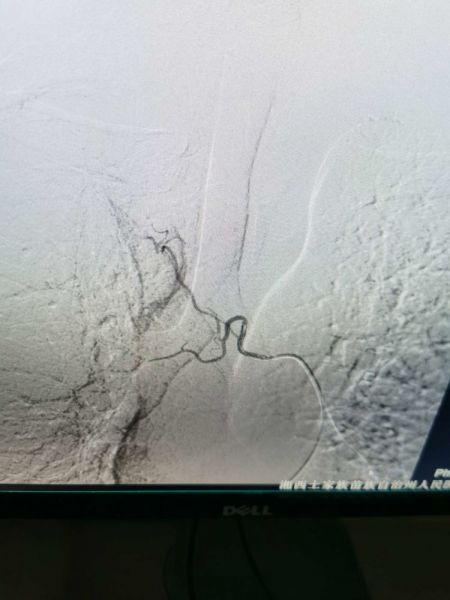

杨某反复咯血十余天,于元月23日住院,入院诊断:肺炎并咯血,结核?高血压病,二型糖尿病。大年三十下午三点三十分急诊手术,DSA示:右上支气管动脉发现多个出血灶。

栓塞后病灶出血停止